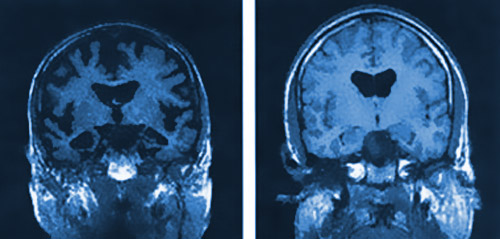

Per ora la ricerca è stata compiuta “solo” su dei (poveri) topi da laboratorio a cui era stato impiantato geneticamente il morbo di Alzheimer e successivamente esposti alle onde elettromagnetiche del cellulare per 2 intervalli al giorno da 1 ora ciascuna. Questo per 8 mesi. Si è scoperto così che le onde hanno stimolato i neuroni, specie nei topi più giovani, contribuendo a far regredire la malattia. In ogni caso, anche gli altri topi hanno mostrato segni di forte rallentamento nello sviluppo dell’Alzheimer.

Sebbene questi risultati non possano ancora far gridare al miracolo, aprono senza dubbio altissime speranze, dato che i topi geneticamente sono molto simili a noi. Rebecca Wood, responsabile dell’Alzheimer’s Research Trust, ha dichiarato: “Questa ricerca è stata effettuata su cavie da laboratorio in quanto in loro il morbo di Alzheimer ha un comportamento che ha moltissimi punti in comune con quello degli esseri umani“.